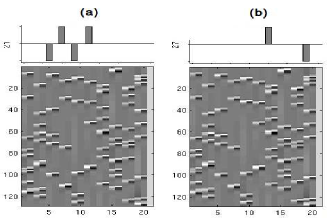

A General Linear Model (GLM) was constructed to capture stimulus-related BOLD response. As shown in Fig. 6, the design matrix relies on ten experimental conditions and is thus made up of twenty one regressors corresponding to stick functions convolved with the canonical Haemodynamic Response Function (HRF) and its first temporal derivative, the last regressor modelling the baseline. This GLM was then fitted to the same acquired images but reconstructed using either the Siemens reconstructor or our own pipeline, which in the following is derived from the early UWR-SENSE method [31] and from its 4D-UWR-SENSE extension we propose here.

the Left click vs. Right click (Lc-Rc) contrast for which we expect evoked activity in the right motor cortex (precentral gyrus, middle frontal gyrus). Indeed, the Lc-Rc contrast defines a compound comparison involving two motor stimuli which are presented either in the visual or auditory modality. This comparison aims therefore at detecting lateralization effect in the motor cortex: see Fig. 6(a).